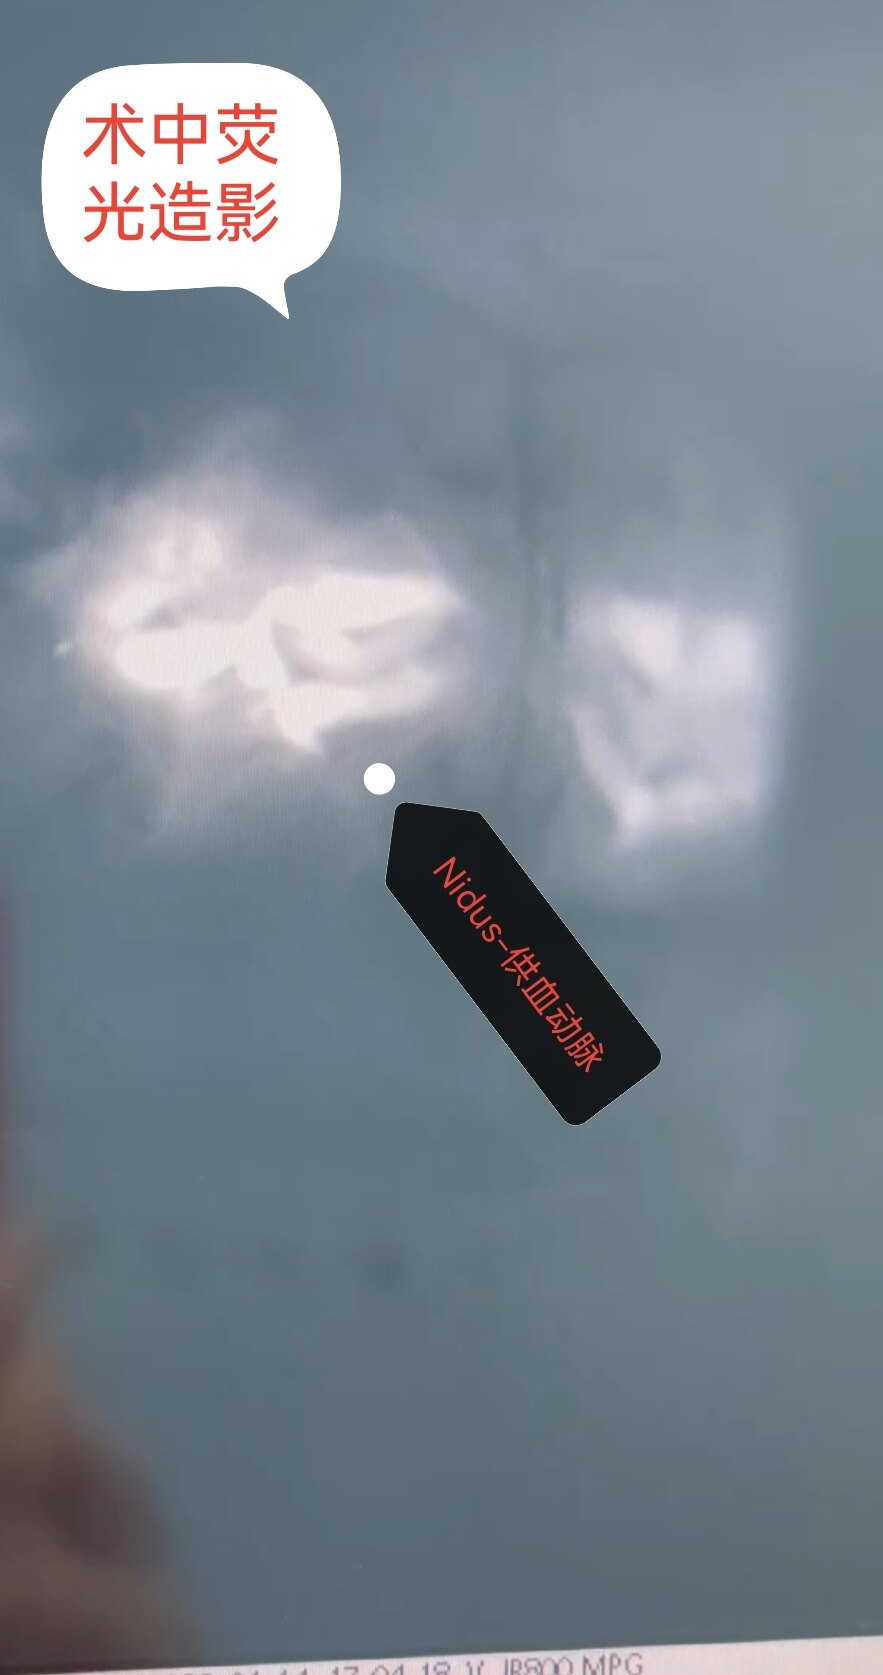

脑血管畸形主要以儿童期和青少年发病为主,儿童主要以头疼、癫痫和出血发病就诊。检查脑CTA、MRA,金标准为全脑血管造影(DSA)。治疗包括DSA介入栓塞(就是我们老百姓常说的微创手术)和开颅畸形团切除术以及伽马刀治疗,各有利弊额,也要更具患儿具体情况个性化定制治疗方案。今日展示一例8岁男童右侧枕叶脑血管畸形(AVM)破裂出血血肿急诊开颅血肿清除+荧光显微镜下畸形团全切手术。患儿入院单侧瞳孔散大,脑疝形成,已不适合介入治疗,甚至复合手术会耽搁救治。现患儿经治疗痊愈出院,无神经功能后遗症表现。后期在造影复查,修补颅骨。